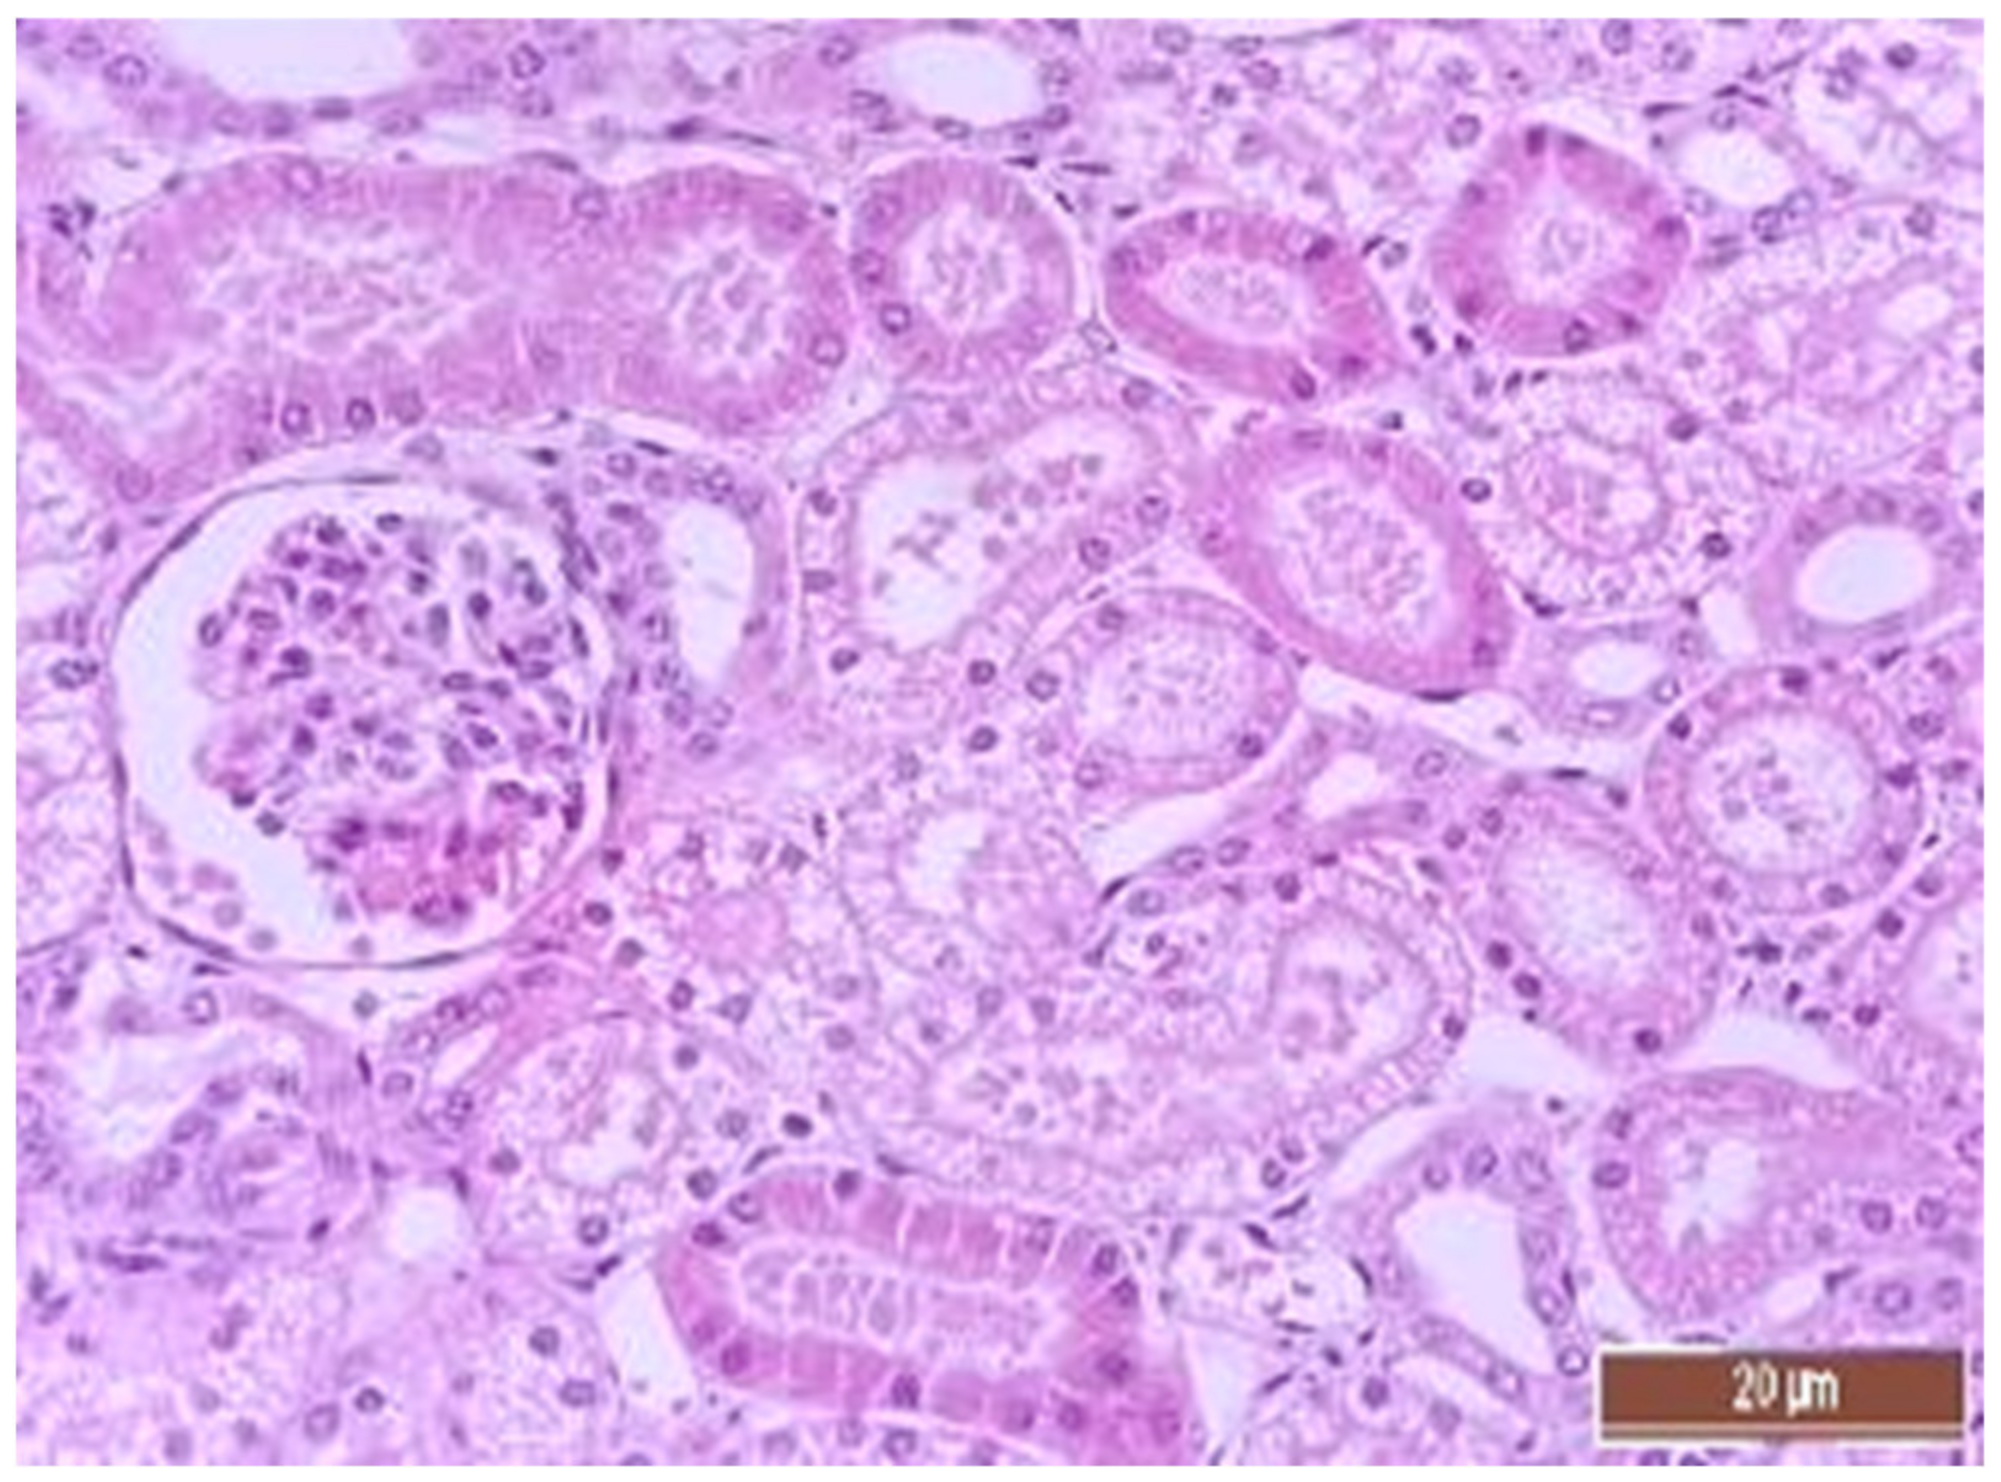

3.4. Pathology of Kidneys

| Dystrophy of the epithelium of the tubules | CPB-contr, n = 25 | 2 (1; 3) | p = 0.49 |

| CPB-NO, n = 25 | 1 (1; 2) | ||

| Lymphoplasmocytic infiltration | CPB-contr, n = 25 | 0 (0; 1) | p = 0.37 |

| CPB-NO, n = 25 | 1 (1; 1) | ||

| Hyperemia | CPB-contr, n = 25 | 2 (2; 3) | p = 0.55 |

| CPB-NO, n = 25 | 3 (2; 3) |